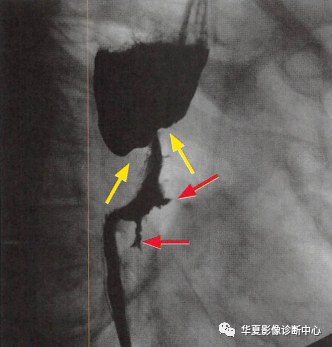

食管癌在鋇餐造影下的一種表現(xiàn)之一,顯示食管局部不規(guī)則狹窄(黃箭頭:玫瑰花花干),近端食管擴張(萎陷的玫瑰花朵),兩個不規(guī)則線狀潰瘍(紅箭頭:玫瑰花葉/刺),形似黑色玫瑰花,小編原創(chuàng)命名為:“黑色玫瑰花征”,幫助記憶,加深映像

食管癌在鋇餐造影下的一種表現(xiàn)之一,顯示食管局部不規(guī)則狹窄(黃箭頭:玫瑰花花干),近端食管擴張(萎陷的玫瑰花朵),兩個不規(guī)則線狀潰瘍(紅箭頭:玫瑰花葉/刺),形似黑色玫瑰花,小編原創(chuàng)命名為:“黑色玫瑰花征”,幫助記憶,加深映像&食管癌表現(xiàn)多樣。